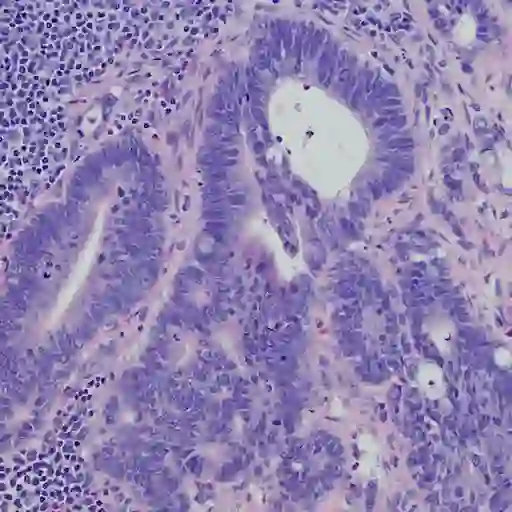

问题6:结肠癌

添加一个癌症UC的诊断似乎非常不公平。但是,根据一项研究世界胃肠病学杂志》上,UC患者的结肠癌的风险增加2%经过10年的疾病30年后的18%。这可能是因为UC炎症损害结肠细胞中的遗传物质,导致突变。唯一的人不必太过担心那些UC是局限于直肠,Hagan博士指出。大多数人能指望拥有结肠镜检查每一两年开始八年后诊断。